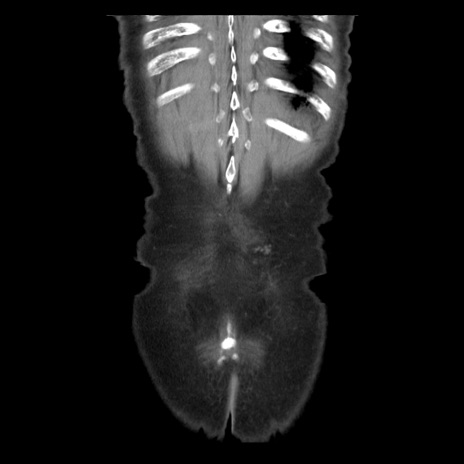

症例21(冠状断像)

横断像